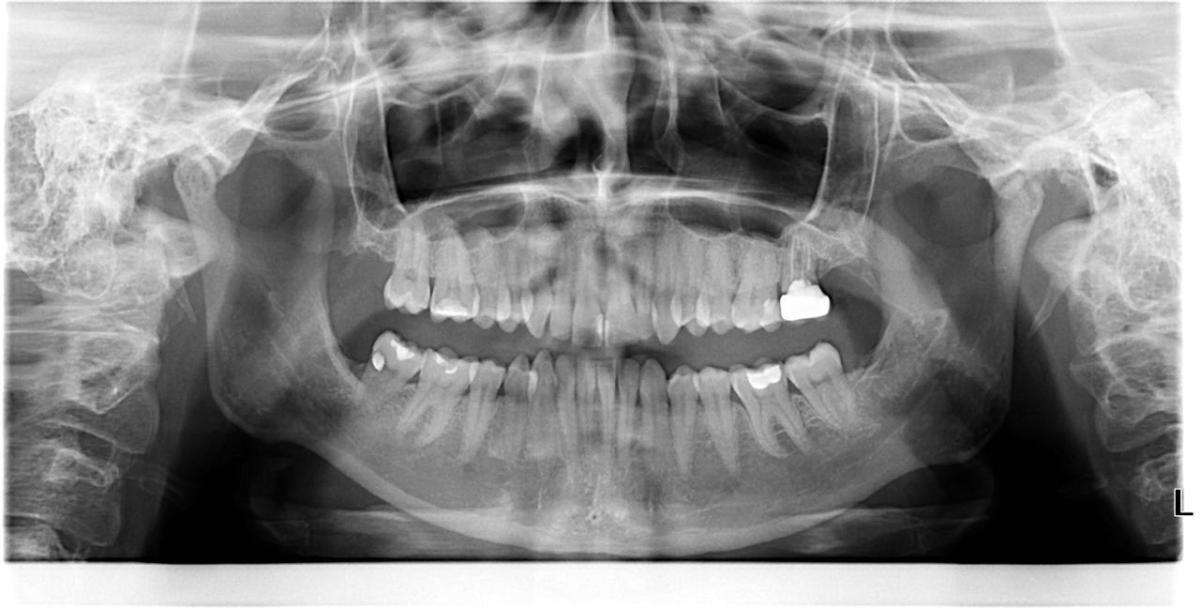

Больше года периодически поднывал зуб сверху справа. При этом я обсолютно нормально ем холодное, горячее, сладкое, сплю, просто чувствую как-будто бы зуб немного тянет вверх. Я думала это зуб 15. В феврале обратилась к стоматологу. Доктор меня осмотрела, сделала прицельный снимок, сказала что с 15 все в порядке, возможно это 16 и нужно удалять нервы. Так же нужно запломбировать зуб 26.

В июле у меня на десне возле зуба 27 появилась припухлость (почувствовала ее я зыком), я испугалась, решила что это что-то с зубом под коронкой (при этом зуб не болел совсем) и побежала к другому врачу. Доктор меня осмотрел, сделал ортопантонограмму, сказал что не знает что с десной, а основная моя проблема — это парадонтит 2 степени. Нужно делать уз чистку и пить витамин С 1000 мг. На вопрос, нужно ли лечить зуб 16, ответил, что не нужно, а зуб 26 — можно полечить. На зуб 27 поставил пломбу и это должно мне помочь с десной.

Пару месяце назад стал давать о себе знать зуб 26 (немного ноет). Обратилась к третьему стоматологу. Жаловалась на зубы 16 и 26. Доктор провел осмотр, смотрел снимок, сказал что не видит причин и не знает почему у меня болят зубы )

Я бы начал с 47...

не пойму я ваших стоматологов .То сплошные СТ , а то банальные периапикал сделать не могут.а по теме . Мне кажется у 14(26) под ДО пломбой есть кариес и уже как бы не пульпит.